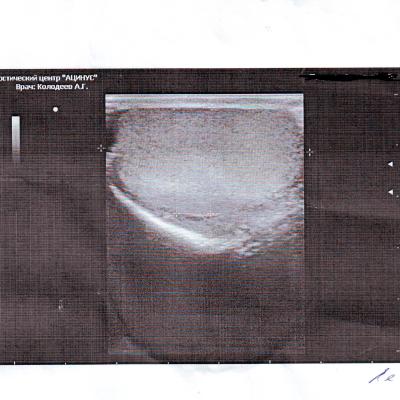

Здравствуйте у меня болели яички особенно левое пошёл к врачу сказал застой простаты, принимал препараты и заметил что яички уменьшились в размерах особенно левое и оно оттягиваеться иногда еще вниз сделал узи как указано в записи всё вроде хорошо так почему не пойму они уменьшились я так понял это атрофия яичек? можно ли восстановить размер?